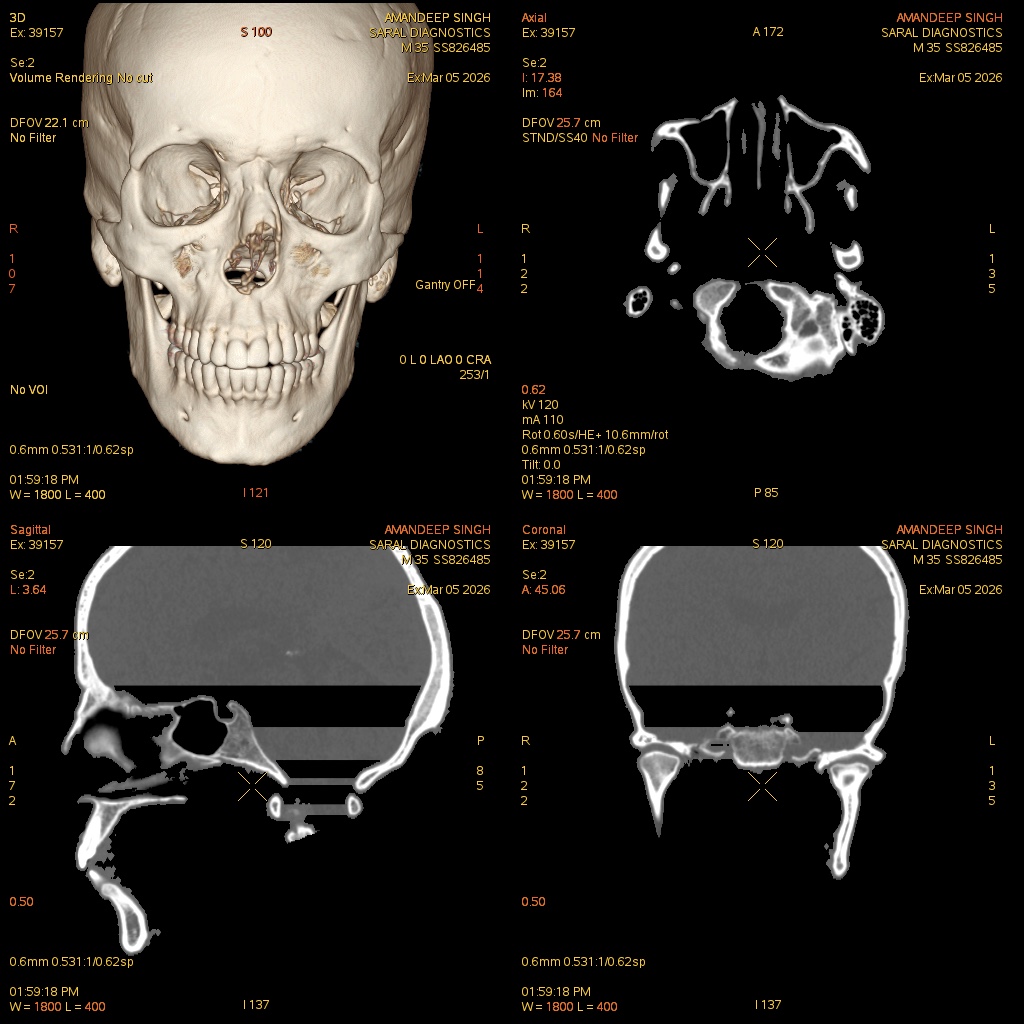

Reference Image

Face Plain

The Face Plain CT scan provides high-resolution images of facial bones, sinuses, and soft tissues without contrast. It is commonly used to evaluate fractures, congenital anomalies, sinus disease, tumors, or trauma. The scan is non-invasive, quick, and safe, providing detailed anatomical images that help clinicians diagnose pathology, plan surgical procedures, or monitor recovery. While contrast is not used, the images allow accurate assessment of bone structures and soft tissue anatomy. This procedure is essential for initial evaluation of facial trauma, infections, or pre-operative planning.